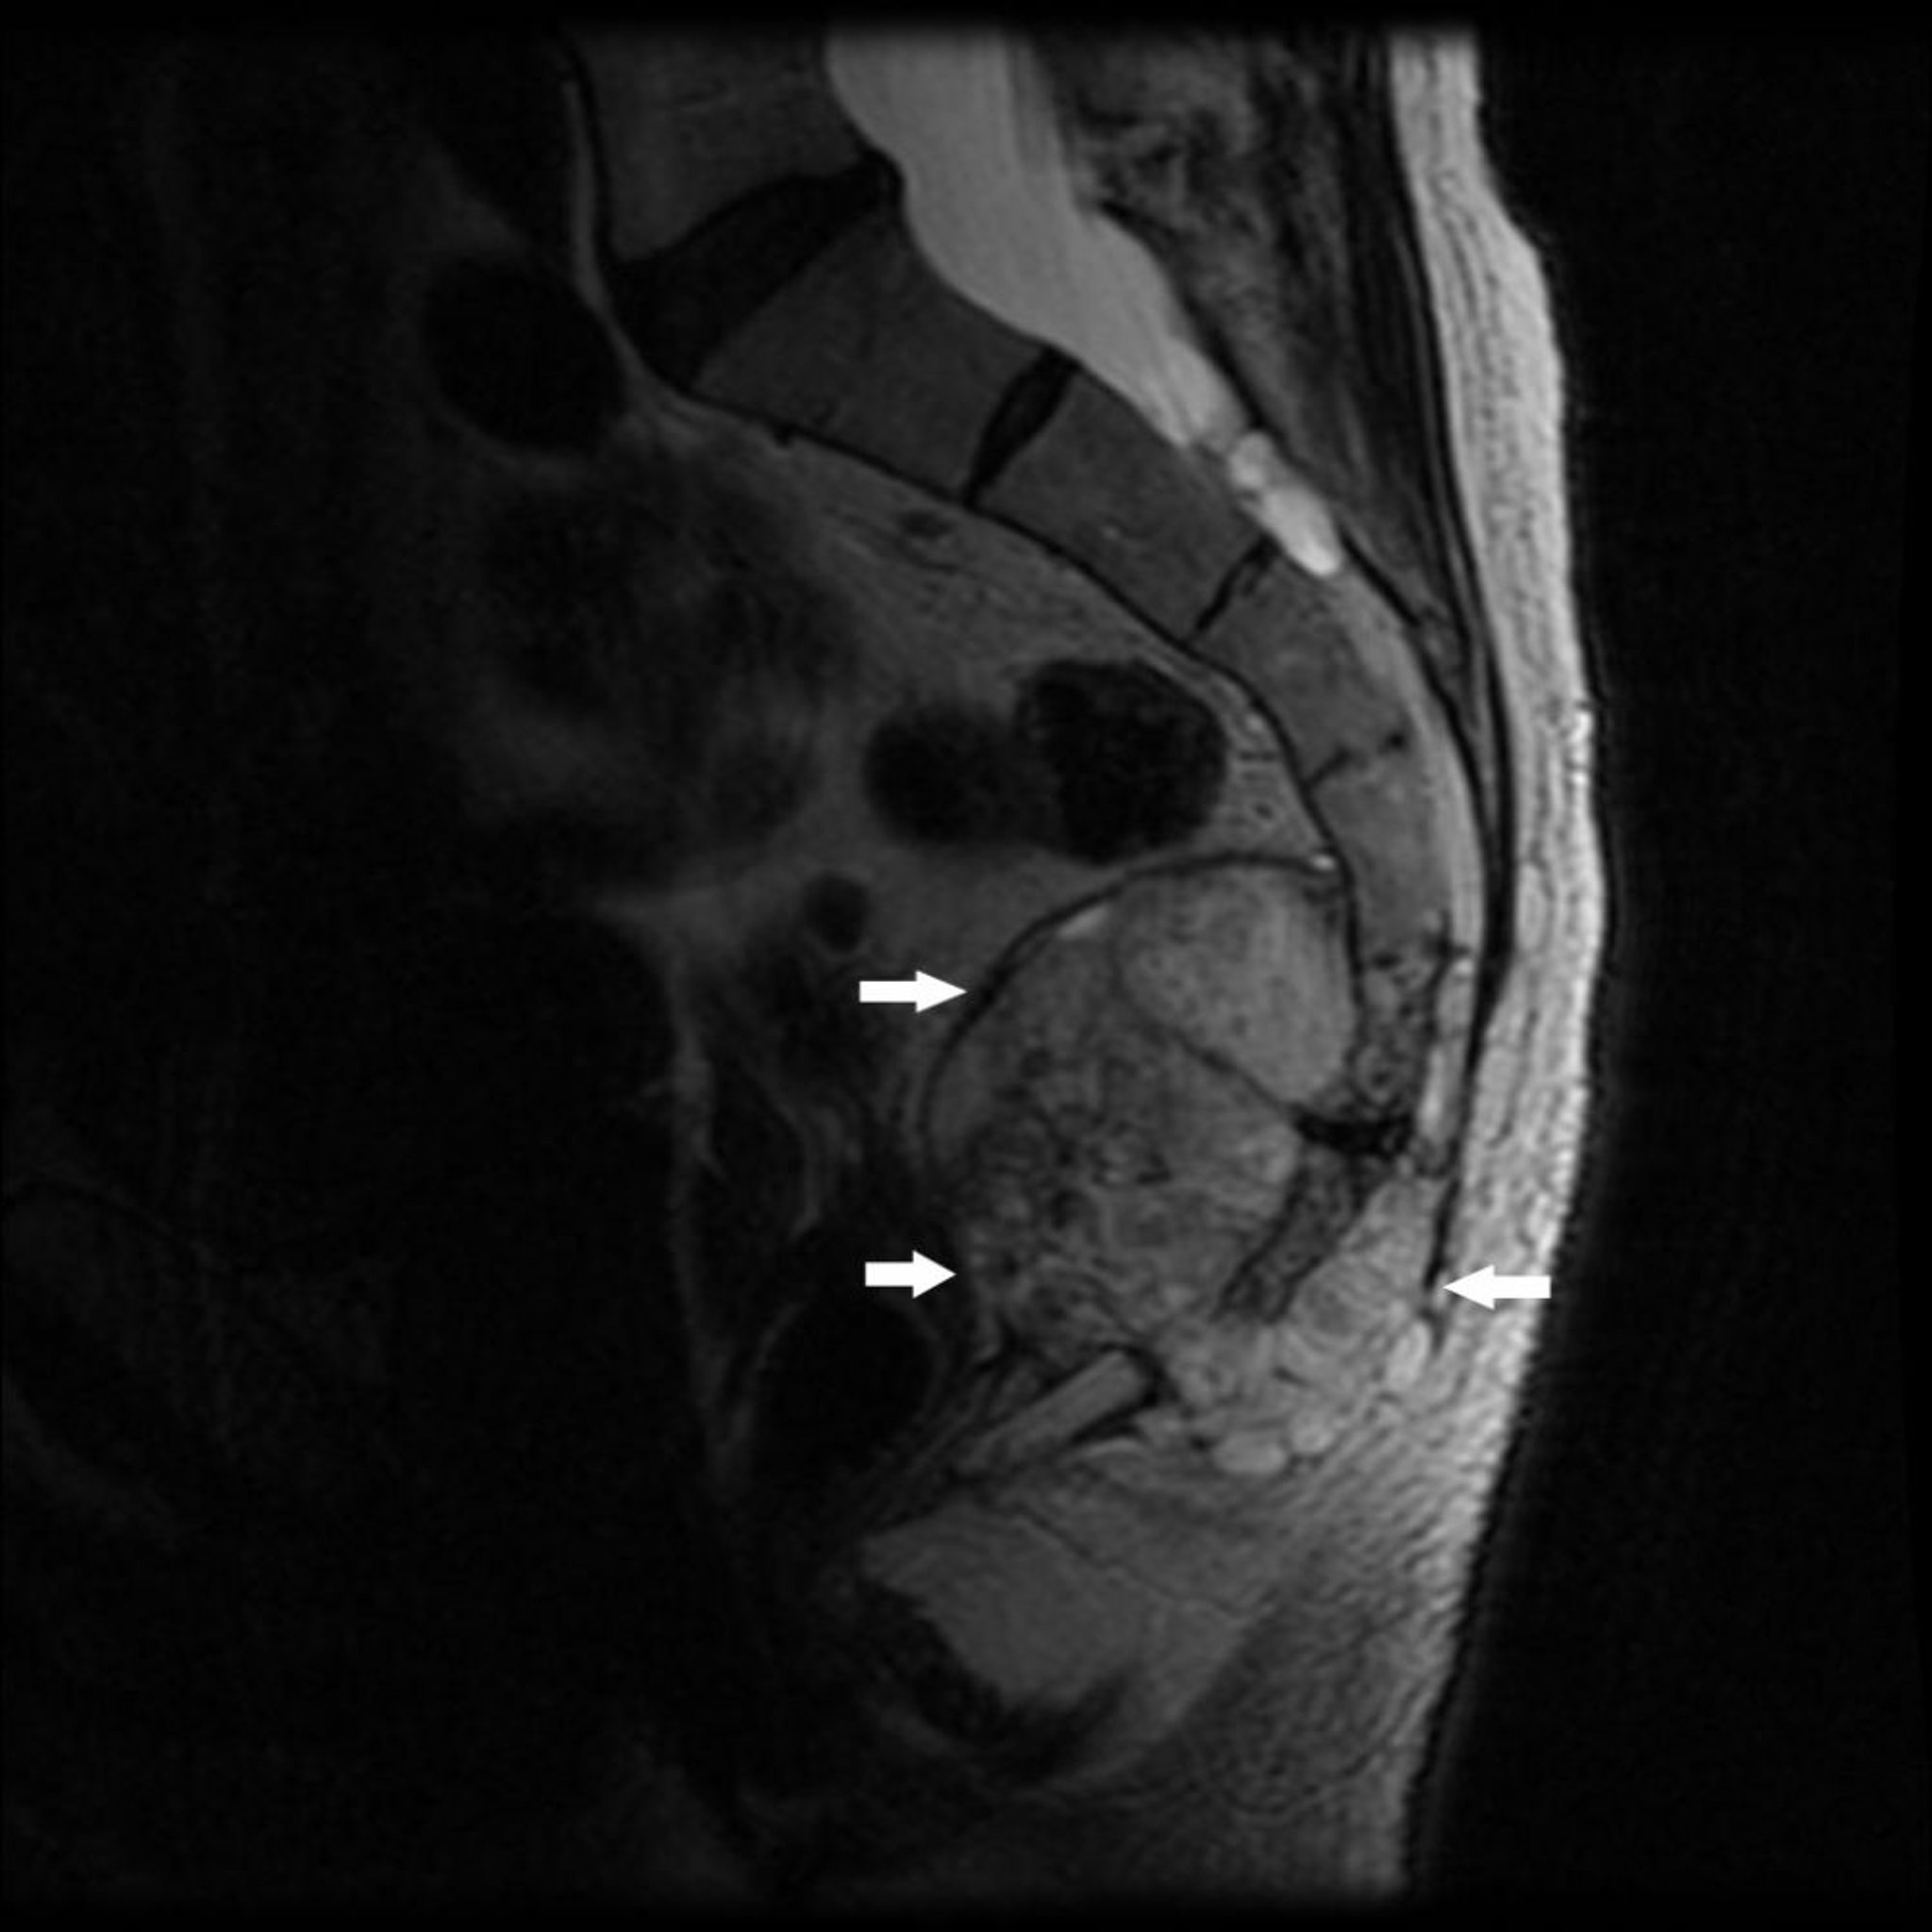

Diese MRT-Aufnahme zeigt einen Tumor am kaudalen Ende des Os sacrum (S4) und des Os coccygis mit Knochenzerstörung und Weichteilraumforderung (Pfeile), typisch für ein Chordom.

Image courtesy of Michael J. Joyce, MD, and Hakan Ilaslan, MD.